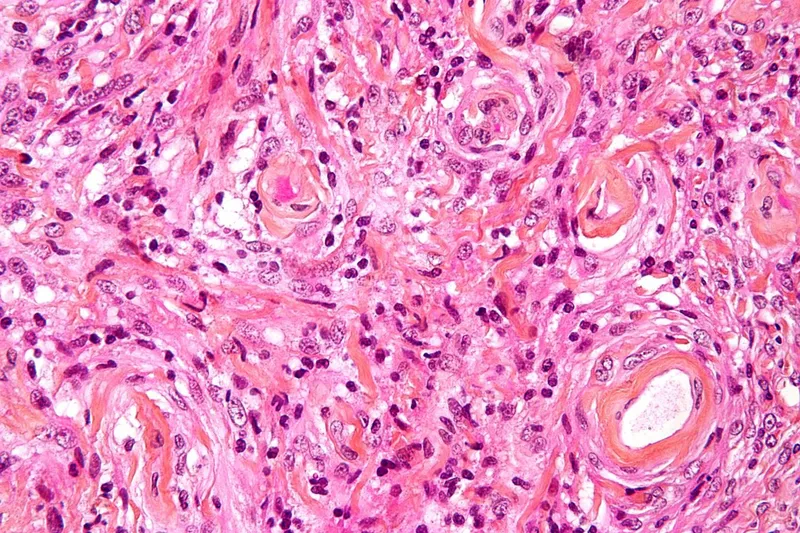

Meningiomas account for 35-40% of skull base tumors, with anterior skull base and sphenoid wing locations predominating. WHO Grade I tumors comprise 80-85% of cases with excellent prognosis following gross total resection. Simpson Grade I-II resection achieves <5% recurrence rates at 10 years.

Chordomas arise from notochordal remnants, predominantly affecting the clivus (35-40%) and sacrococcygeal region (50-55%). These locally aggressive tumors demonstrate high recurrence rates (30-50%) following subtotal resection. Proton beam radiotherapy combined with maximal safe resection optimizes local control achieving 80-85% five-year progression-free survival.

Esthesioneuroblastoma represents rare olfactory neoplasms (<5% skull base tumors) with bimodal age distribution and high metastatic potential. Kadish staging (A-D) correlates with prognosis: Stage A >90% five-year survival, Stage D <40% survival. Combined surgical resection and adjuvant radiotherapy achieve optimal outcomes.

Juvenile nasopharyngeal angiofibroma affects adolescent males exclusively, demonstrating characteristic vascular enhancement and aggressive local growth. Preoperative embolization reduces intraoperative blood loss from >2000mL to <500mL. Endoscopic resection achieves >95% cure rates with minimal morbidity in experienced centers.

Molecular markers increasingly guide treatment decisions - IDH mutations in skull base gliomas, BRAF mutations in craniopharyngiomas, and chromosomal alterations in chordomas provide prognostic information and targeted therapy opportunities.